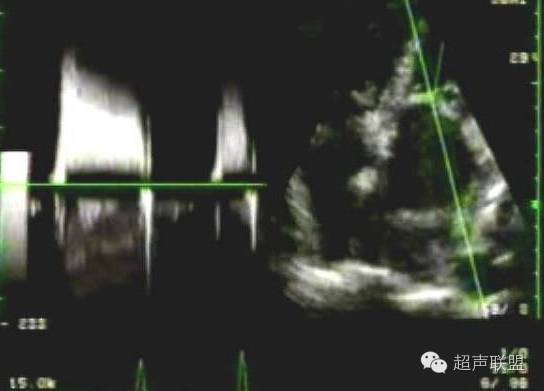

()压差减半时间法

对典型的二尖瓣狭窄频谱,利用经验公式MVA= 220/ PHT可以测量自然瓣二尖瓣狭窄瓣口的面积。当频谱曲线呈非线性斜率时,舒张早期或晚期出现小的尖峰,测量时则以舒张中期的斜率及其外延为准。亦有直接用压差减半时间评估二尖瓣狭窄程度。压差减半时间法估价二尖瓣狭窄程度重复性好,观察者之间及观察者个人的误差很小。但PHT是反比例函数,狭窄程度越重,结果越准确。正常瓣膜不能用PHT评估。房颤患者,避免测量舒张期短的频谱,取5个心动周期的平均值。出现双峰时,测量舒张中期的下降支以其外延为准,保证足够的压力减半时间。在心动过速、左心室顺应性出现异常变化,合并主动脉瓣反流或二尖瓣成形术或球囊扩张术后时,多数不能准确测量瓣口的面积。尤其值得强调的是,在评估二尖瓣位人工瓣有效瓣口面积时,不宜应用上述经验公式。因为此公式不是逻辑推导的,而是依据自然瓣的观测结果所获得的“经验”公式,仅适用于计算自然瓣瓣口面积,而不能用于计算人工瓣的瓣口面积。

二尖瓣血流频谱下降支呈非线性(有转折)形态,用PHT法测算二尖瓣口面积时,下降斜率的描计部位不应是早期节段的斜率,而应该在中间以下的线性节段。